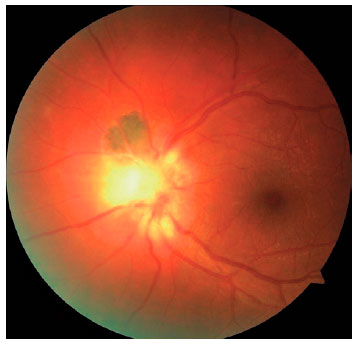

We classified optic nerve involvement due to OT as published by Eckert et al.(10). Accordingly, we formed four groups: (1) involvement secondary to distant active retinitis lesions (Figure 1), (2) involvement secondary to the activation of juxtapapillary lesions (Figure 2), (3) papillitis (Figure 3), and (4) neuroretinitis (papillomacular or serous macular detachment with hard exudates at the macula and optic nerve involvement) (Figure 4).

The optic nerve involvements were detected either at admission or during the follow-up in 17 (14.4%) of the 118 reviewed 118 cases diagnosed as having OT. The mean age of the 17 cases (12 women and 5 men) was 25.35 ± 7.76 years (range, 9 39 years). Their follow-up duration ranged between 2 and 112 months (mean, 33.33 ± 36.10 months). Fifteen cases were diagnosed as having recurrent OT, and two (cases 13 and 14) as having primary OT. We found 12 (70.5%) patients had a lesion (juxtapapillary) in the neighborhood of the optic nerve, 2 (11.7%) had direct involvement (papillitis), 2 (11.7%) had neuroretinitis, and 1 (5.8%) had involvement secondary to a distant active lesion (Table 1). OT was unilateral in the majority of cases (94.1%), and only one case had an old retinochoroidal scar in both ocular fundi (case 1, with a congenital OT infection) with optic nerve involvement in the left eye, but not in the right eye.

Toxoplasmosis-associated optic nerve involvement can be divided into three groups: The first one is associated with a distant active lesion, the second one is associated with activation in the neighborhood of a peripapillary old scar, and the third one results from direct optic nerve involvement. In addition, the third group is divided into two subgroups as papillitis and neuroretinitis, depending on the presence/absence of macular involvement. In the largest case series study to date, optic nerve involvement was most commonly encountered as secondary to a distant active lesion, followed by cases secondary to the activation of an old peripapillary scar, and finally by cases resulting from direct involvement(10). In contrast, Tutkun et al reported active lesion sites in the juxtapapillary region or in the region closest to the optic disc in all their patients with optic nerve involvement(19). In our series, the activation of an old pigmented lesion in the juxtapapillary region was the most common type of optic nerve involvement. The time to diagnosis, time to treatment onset, immune status of the patient, and genotypic variety of the parasite may play a role in the different types of optic nerve involvement.